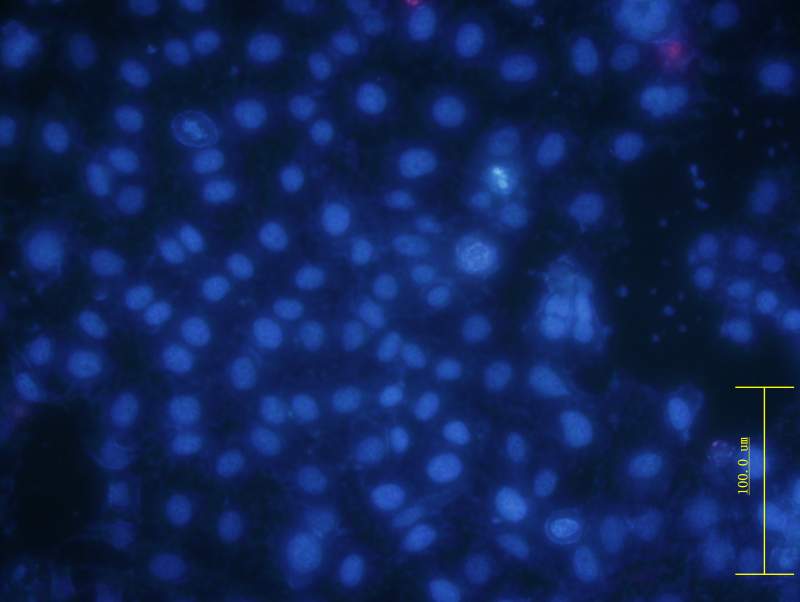

ϸ°û¾­¹ýÎïÀí½áºÏ»¯Ñ§ÁÆ·¨36 Сʱºó£¬ ÓÃhoechst Ⱦɫ ºÍPIȾɫ£¬¹Û²ìÆÚÐÎ̬¡£

Õý³£Ï¸°û.jpg

ÓÐË¿·ÖÁÑÔÖÄÑ£¬ÍíÆÚµòÍö£¬»µËÀ£¿